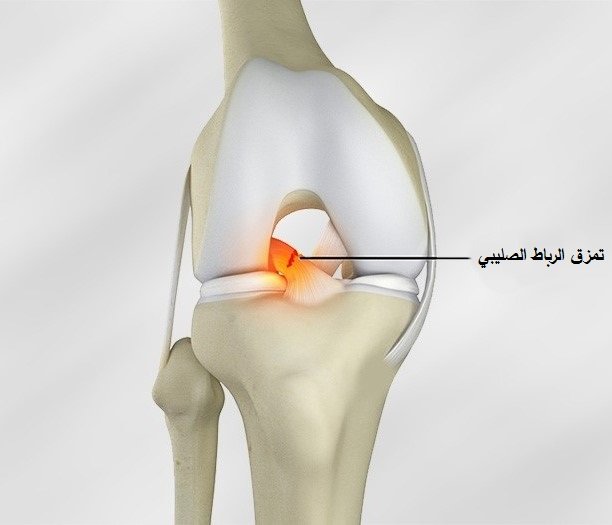

- قطع الرباط الصليبي الأمامي: من أخطر إصابات الملاعب، ويحدث غالبًا مع التوقف المفاجئ أو تغيير الاتجاه السريع، ويؤدي إلى عدم ثبات مفصل الركبة.

تحدث إصابات الأربطة نتيجة التواء مفاجئ أو سقوط خاطئ أو احتكاك مباشر مع لاعب آخر. وهي إصابات شائعة جدًا ضمن إصابات ملاعب كرة القدم على وجه الخصوص. وتتفاوت شدة الإصابة بين تمدد بسيط في الأربطة وتمزق كامل يحتاج إلى تدخل طبي متخصص.

علاج إصابات الأربطة

يعتمد العلاج على شدة التمزق، ففي الإصابات البسيطة يمكن الاكتفاء بالعلاج التحفظي والعلاج الطبيعي ودعامات المفصل.

أما في حالات التمزق الكامل أو عدم استقرار المفصل، فقد يكون التدخل الجراحي هو الحل الأمثل.

بعد العلاج الجراحي أو التحفظي، يأتي دور التأهيل الحركي الذي يهدف إلى استعادة قوة العضلات المحيطة بالمفصل وتحقيق الثبات المطلوب للعودة الآمنة للنشاط الرياضي.